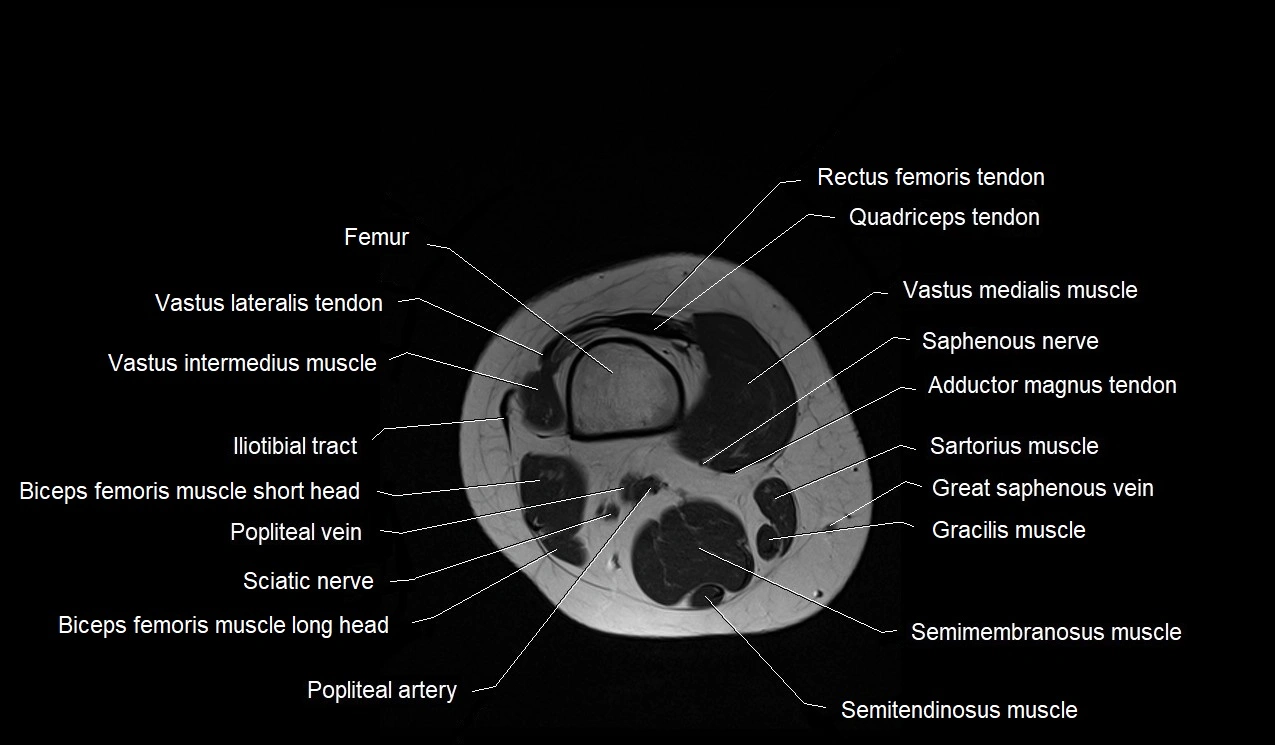

- Biceps femoris muscle (Long head)

- Biceps femoris muscle (Short head)

- Distal rectus femoris tendon

- Distal vastus intermedius tendon

- Distal vastus lateralis tendon

- Distal vastus medialis tendon

- Femur

- Gracilis muscle

- Iliotibial tract

- Popliteal artery

- Popliteal vein

- Rectus femoris muscle

- Saphenous nerve

- Sartorius muscle

- Semimembranosus muscle

- Semitendinosus muscle

- Vastus intermedius muscle

- Vastus lateralis muscle

- Vastus medialis muscle